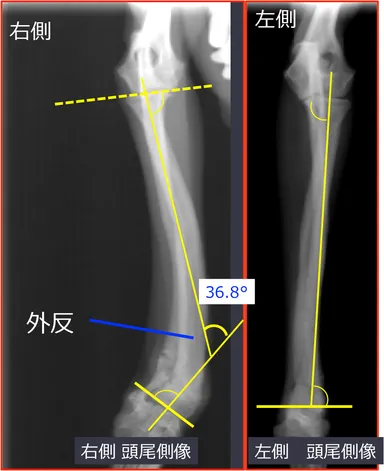

<術後8週 歩様>

・外観での右側前肢の外反も改善しており、歩様良好。

術前と術後の比較

http://www.atpress.ne.jp/releases/54567/img_54567_7.jpg

・骨切り部の良好な癒合所見。インプラントに異常は認められない。